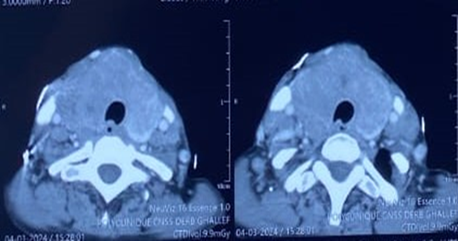

A

cervicothoracic CT scan was ordered (because of the strong suspicion of

anaplastic carcinoma), which showed a general increase in the size of the

thyroid with multiple nodules, especially in the right lobe slightly plunging

towards the upper mediastinum and pushing the adjacent tissue structures,

moreover, the examination did not reveal any pulmonary involvement or

cervico-mediastinal lymphadenopathy (Figure

1).

Figure1: Axial

CT images showing: an enlarged thyroid gland extending beyond the

cervicothoracic contour Biological